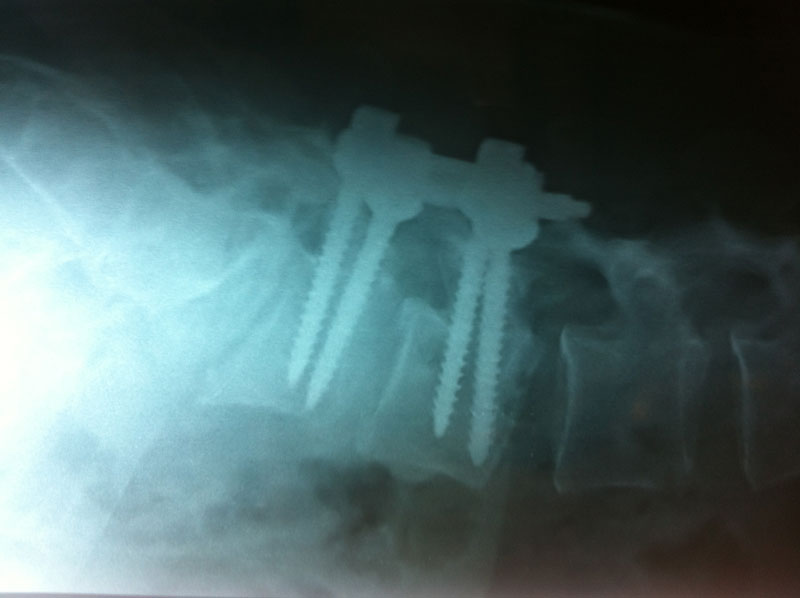

Surgery may be recommended if the conservative treatment options do not provide relief within two to three months. If leg or back pain limits normal activity, if there is weakness or numbness in the legs, if it is difficult to walk or stand, or if medication or physical therapy is ineffective, surgery may be necessary, most often spinal fusion.